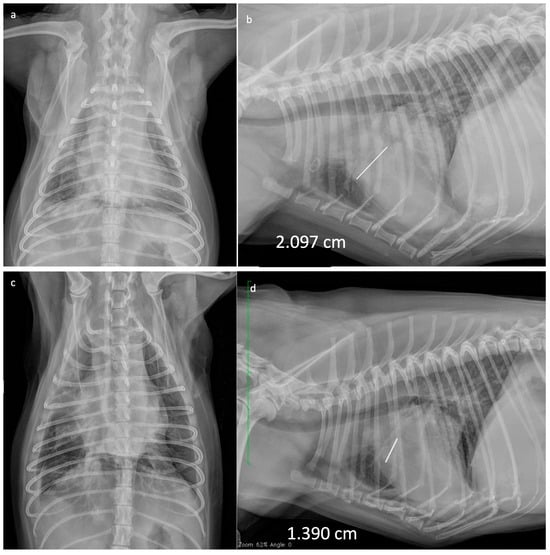

| N° | Clinical Signs | Pleural Effusion | Tumour Location | Total Number of VRL Administrations | VCOG Toxicity | TTP (Days) | ST (Days) |

|---|---|---|---|---|---|---|---|

| 1 | None | NO | Pulmonary + Hepatic Mts | 8 | A grade II V grade I | 88 | 160 |

| 2 | Dyspnea | YES | Diffuse Pulmonary | 8 * | N grade IV V grade I | 84 | 635 |

| 3 | Weight Loss | NO | Diffuse Pulmonary | 10 | NO | 112 | 120 |

| 4 | Weight Loss | NO | Hepatic Mts | 8 | NO | 90 | 90 |

| 5 | Dyspnea | YES | Diffuse Pulmonary + Hepatic Mts | 1 | NV | 7 | 7 |

| 6 | Cough | NO | Diffuse Pulmonary | 8 * | N grade II | 84 | 100 |

| 7 | Weight Loss | NO | Diffuse Pulmonary | 8 * | NO | 90 | 90 |

| 8 | None | NO | Diffuse Pulmonary | 9 | N grade II | 98 | 100 |

| 9 | Dyspnea | YES | Diffuse Pulmonary | 8 | N grade I | 84 | 90 |

| 10 | None | NO | Diffuse Pulmonary | 10 | N grade I | 112 | 120 |